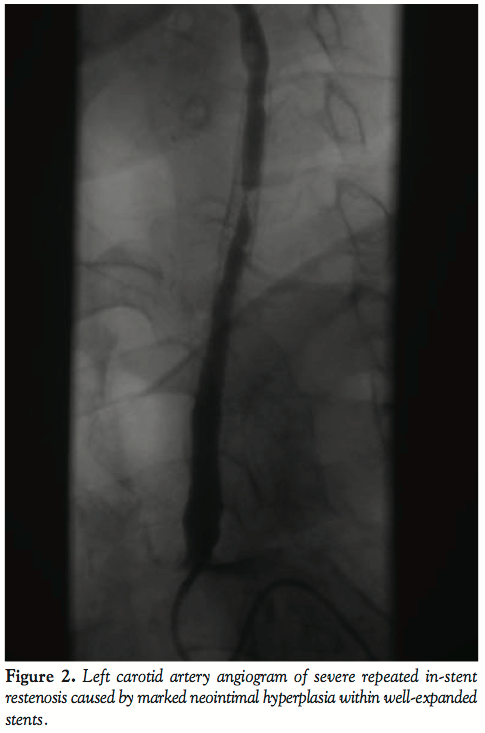

At the time of first visit in our institution, the patient was on aspirin and low-dose corticosteroids. Her laboratory results were unremarkable (including CRP and erythrocyte sedimentation rate) as well as her physical examination except for pulseless left radial artery. Angiography showed calcification of the aorta without significant aortic disease and patent right innominate artery as well as its branches. The left common carotid artery was found to have severe eccentric in-stent restenosis (Figure 1). The left internal carotid artery examination was without significant abnormalities while left external carotid artery was occluded. The left subclavian artery was occluded distal to the otherwise normal left vertebral artery. The left axillary artery was fed through dense collaterals from the proximal subclavian artery. Finally, her renal and coronary arteries were without significant signs of disease. Carotid stenting was performed with 2 bare metal carotid stents (Xact, Abbott Vascular) implanted into the left common carotid artery and covering the in-stent restenosis with residual stenosis of less than 20%. Since that time, she has been regularly followed-up by our experienced carotid ultrasound specialist (PZ).